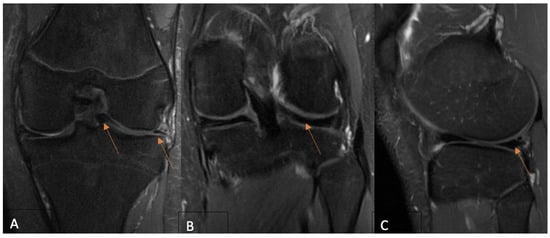

2.2. MRI Evaluation Protocol